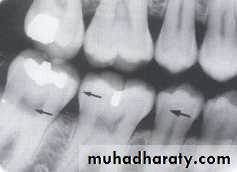

PULP CAVITY: The pulp cavity consist of a pulp chamber and pulp canals, its contain blood vessels, nerve and lymphatic and appears relatively radiolucent on dental radiograph.